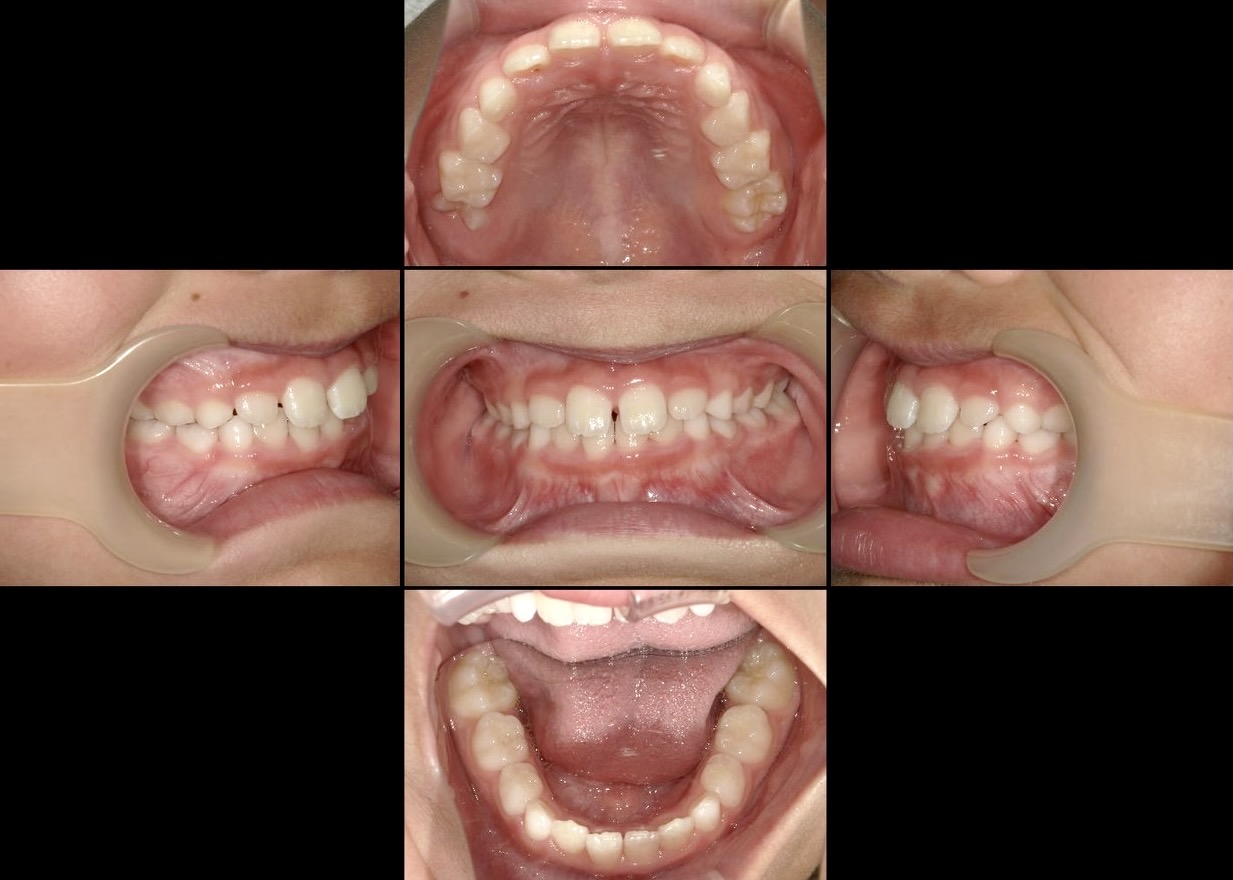

3か月で見えた変化

SHISEIアカデミーに通い始めて3か月。

姿勢が整い、呼吸が安定し、舌が正しい位置に安定してきたお子さんがいます。

そして、受け口に改善が見られたケースもあります。

⬇︎

私たちは歯だけを動かしたのではありません。

“育つ方向”を整えたのです。